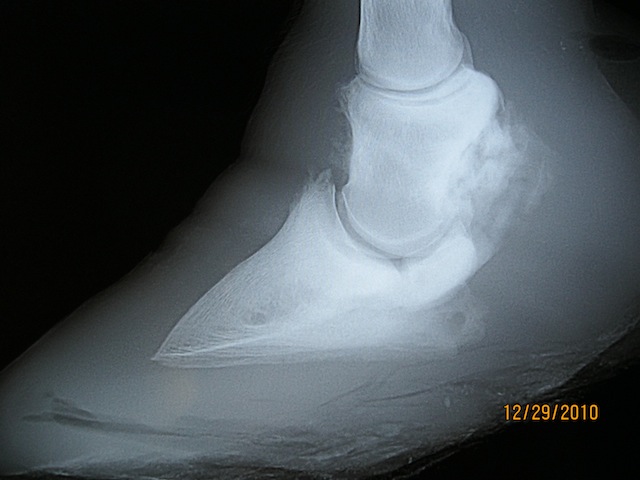

Mister taught me that although the foot you see above looks really good compared to what he had when I met him, looks did not function well for him. I watched the video I took of him over and over. I could see that his joint had no motion and that he was more comfortable rocking back on his heels. After much thought, I decided to try and shape his foot like a rocking chair to see if that would give him some motion to the limb and improve his overall way of moving. It looked funky- not as nice as the foot after the second trim, but it really worked well for him. He was even able to trot! Not sound or even graceful, but for him it worked.

I have to say that he had a great attitude through this whole process. I knew we were not going to fix or cure anything. Did I help to improve his quality of life? yes- and that was the goal.

He did begin to abscess in 3 locations as the structures that fell out of alignment within his foot continued to deteriorate. He was humanely euthanized summer of 2012. I am thankful for the opportunity both he and his owners gave me to learn some valuable lessons that I can take to other horses.